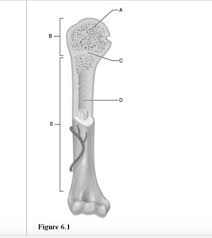

The epiphyseal line is a remnant of the epiphyseal plate, a cartilaginous growth plate that helps bones grow longer during childhood and adolescence. Once a person reaches adulthood, the growth plates close and are replaced by bone, forming the epiphyseal line. While it doesn’t play an active role in bone function, the epiphyseal line marks the boundary between the epiphysis and diaphysis of a long bone.

Epiphysis: The end of a long bone, like the ends of your femur (thigh bone) or humerus (upper arm bone).

Diaphysis: The main shaft of a long bone.

Epiphyseal line: The bony line that forms when the epiphyseal plate closes and stops growing. It indicates the boundary between the epiphysis and diaphysis.

The epiphyseal line indicates the location of the former epiphyseal plate.

The epiphyseal plate, also known as the growth plate, is a layer of hyaline cartilage found in children and adolescents at the ends of long bones. It’s located in the metaphysis, which is the region between the diaphysis (the shaft of the bone) and the epiphysis (the end of the bone).

– Structural Importance: The epiphyseal line serves as a landmark in the bone, indicating the former site of growth. It’s crucial for understanding bone development and any potential growth abnormalities.

In essence, the epiphyseal line is a permanent mark that shows where the epiphyseal plate used to be. It’s a clear indication that the bone has reached its full length and is no longer growing.